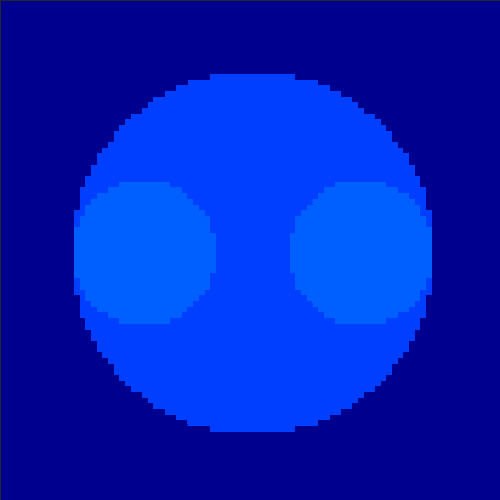

5.2 Monte Carlo Simulation

In order to test the behaviour of the proposed method in a more realistic, random-based test case, we performed a Monte Carlo simulation for dynamic SPECT imaging. First, we created a simple image phantom consisting of an outer and two inner circles which represents the structure of the region of interest (see figure 8(a)). Within those regions we assumed concentration curves over a time period of 90 time steps as displayed in figure 8(b). Based on the tracer intensity in an image frame at each time step, we created a variable number of random decay events (where the number is proportional to the average concentration in one pixel in the whole image frame per time step) with a probability proportional to the concentration in every subregion. They are detected by a virtual double head gamma camera rotating around the patient by 46 degrees per time step, which consists of 374 detector bins. Every simulated decay event is projected onto the scanner and counted by the corresponding detector bin.

In two different tests we fixed the number of events counted by the detector equal to (resp. ) times the average concentration in one pixel. The resulting sinogram images of the accumulated counts in each bin are shown in figure 9.

Based on the sinogram data we applied the proposed algorithm in order to reconstruct the original image sequence. The results for both test cases are shown in figure 10.

As one can see, the method is able to reconstruct the regions properly, even in case of a low count number. Within a number of iterations (average of 100 outer and 10000 inner iterations), the algorithm presents a reasonable reconstruction of the region of interest and the corresponding regional tracer concentration curves. Here, the parameters were not optimized as in the case of the synthesized data sets in the previous section, but kept fixed as , and . With futher optimized parameter values one could possibly provide even better results.